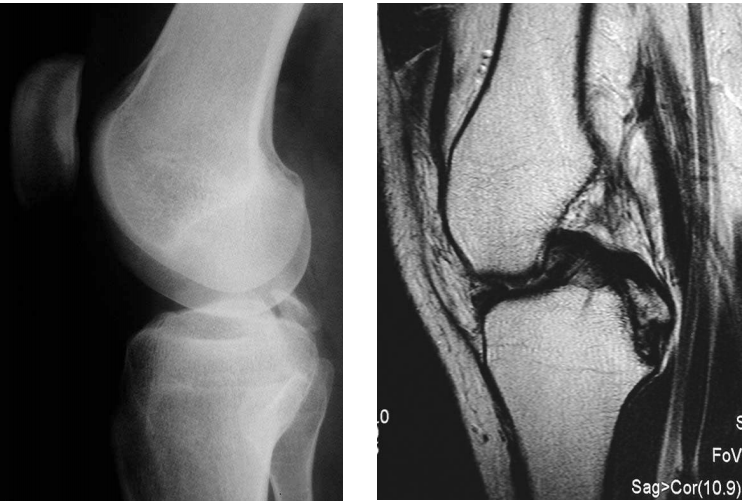

72 一位 22 歲男性病人主訴運動後右膝關節疼痛。圖為本次就診之右膝關節 X 光攝影及磁振造影。最可 能的診斷為何?

(A) Avulsion of medial collateral ligament (B) Avulsion of lateral collateral ligament (C) Avulsion of anterior cruciate ligament (D) Avulsion of posterior cruciate ligament